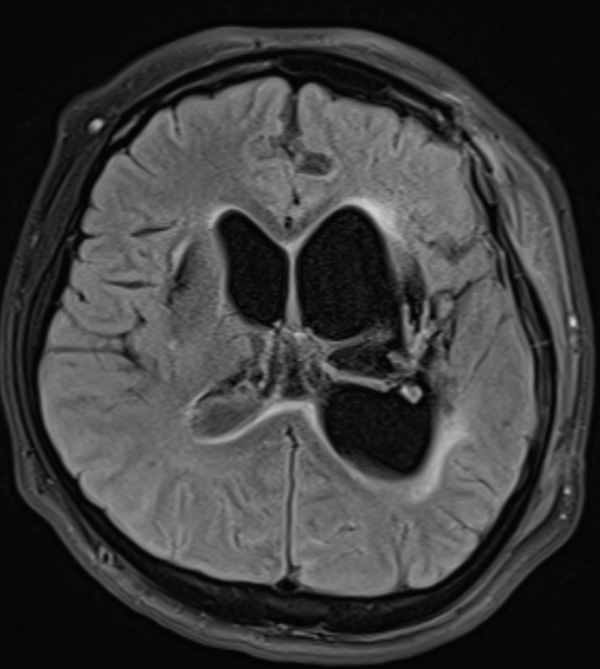

9.MRI에서 나타나는 대표소견 아래와 같이 나타남.

FLAIR : intraventricular debris layering

T1 contrast : ependymal enhancement

DWI : restricted diffusion (pus)

Hydrocephalus

뇌실염 MRI에서 ependymal enhancement + intraventricular debris 가 특징적, EVD 및 Shunt 삽입력이 있으면 뇌실염 가능성이 훨씬 높음.